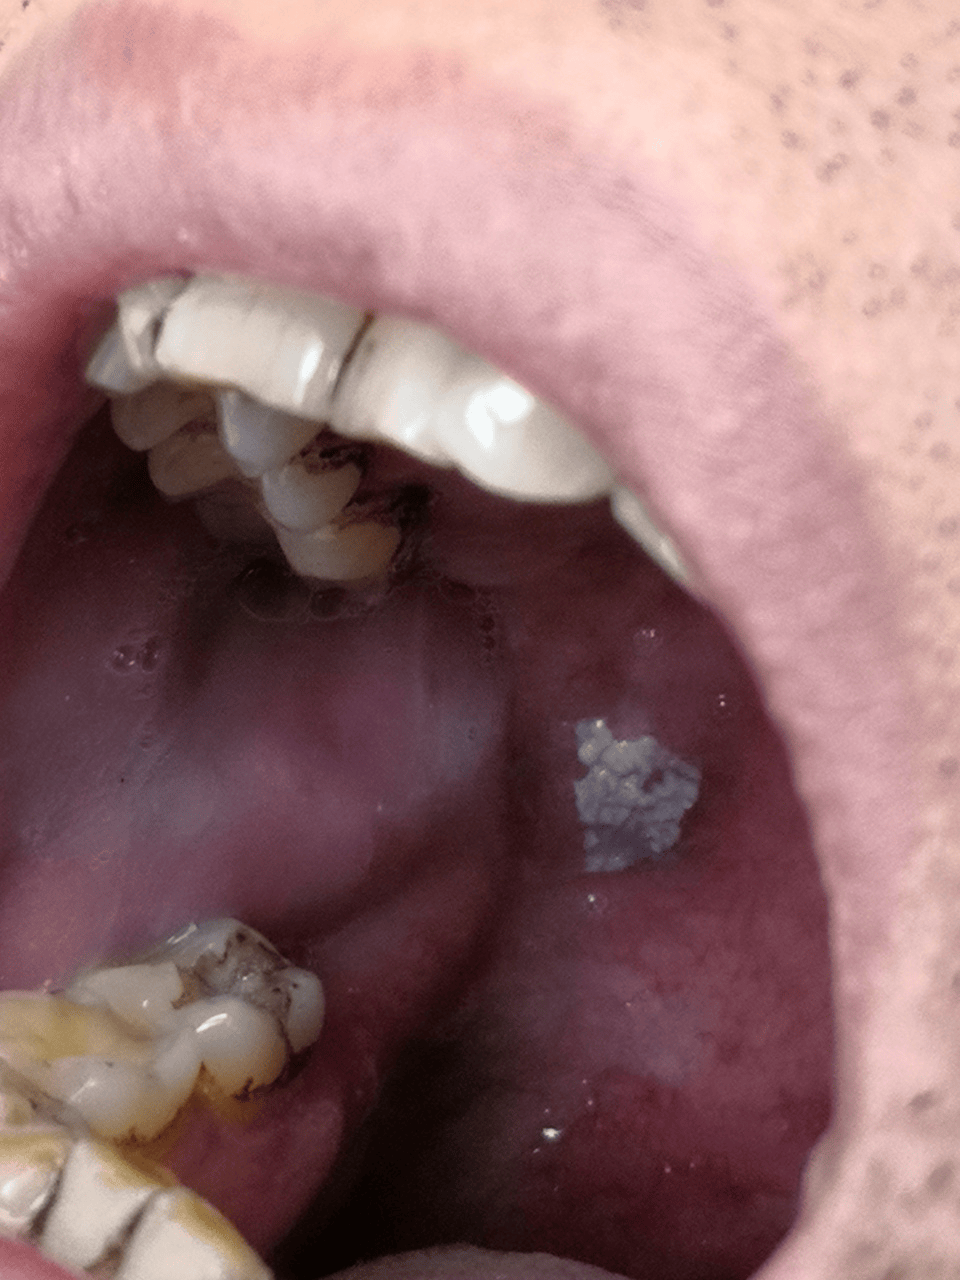

口腔白塞氏病症状图

正文 2017年3月去北京口腔医院就诊,确诊为白塞氏病.

白塞氏病患者的溃疡形态与口腔溃疡相似,但反复性不似口腔溃疡强.